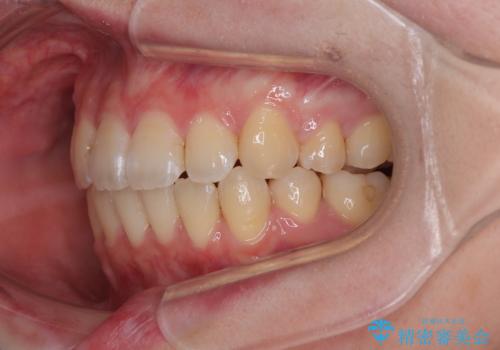

- 上下前歯のデコボコを気にして来院された患者様です。

口元の突出感はあまりなかったものの、デコボコを非抜歯で改善すると出っ歯になる可能性があるため、上下左右の第一小臼歯4本を抜歯し、ワイヤー装置にて矯正治療を行うこととしました。

口元の突出感はなかったものの、捻転や八重歯を改善するために補助装置を併用する必要がありました。

予定の2年半を越えてしまいましたが、無事にきれいな口元に仕上げることができました。